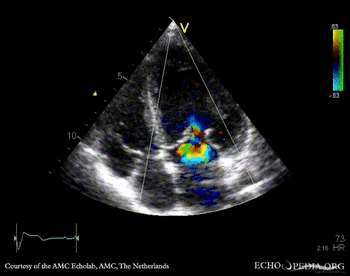

| PLAX: color doppler, mitral regurgitation

PSAX